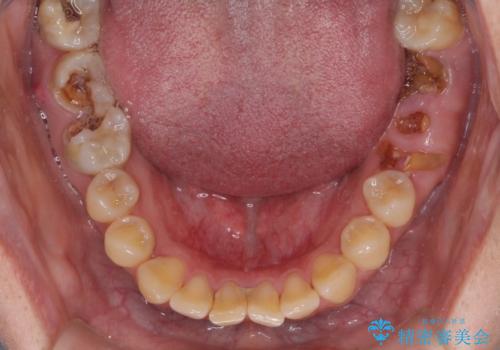

- 奥歯に問題が多くて困っているとのことで来院された患者様です。

開咬により奥歯のみが接触している状態で、前歯部にほとんど接触のない状態で、奥歯に非常に負担のかかる咬み合わせでした。

また、欠損や根管治療の必要な歯など、むし歯による問題も多く散見されました。

まずはむし歯の治療を行い、その後ワイヤー矯正にて咬み合わせを改善し、途中インプラント埋入を行い、矯正治療後に補綴治療を行うこととしました。